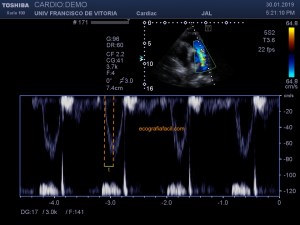

139. Ecocardiografía. Estudio Paraesternal Eje Largo.

141. Mediciones de los planos paraesternales.